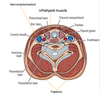

Name the fascia:

Identify the fascial layers surrounding the 4 facial compartments:

1st compartment: area surrounded by investing layer

2nd compartment: area surrounded by pre-vertebral layer

3rd compartment (visceral compartment): area surrounded by pre-tracheal layer

4th compartment: area surrounded by carotid sheath

Neck: Investing Layer of Deep Fascia

name the 2 superior attachments:

external occipital protuberance

superior nuchal line

Neck: Investing Layer of Deep Fascia

name the 4 inferior attachments:

scapular spine

acromion

clavicle

manubrium

Neck: Investing Layer of Deep Fascia

name the 2 posterior attachments:

ligamentum nuchae

spinous process of C7 vertebra

Neck: Investing Layer of Deep Fascia

name the 2 lateral attachments:

mastoid process

zygomatic arch

Neck: Investing Layer of Deep Fascia

(facts)

- splits to enclose sternocleidomastoid and trapezius

- surrounds infrahyoid muscles anteriorly

- forms the roof of the posterior triangle of neck

- goes from base of skull to superior thorax

- forms fibrous capsule of parotid gland

- is pierced by blood vessels (external + anterior jugular vv.) and nerves (lesser occipital, great auricular, transverse cervical, supraclavicular nn., and all branches of cervical plexus)